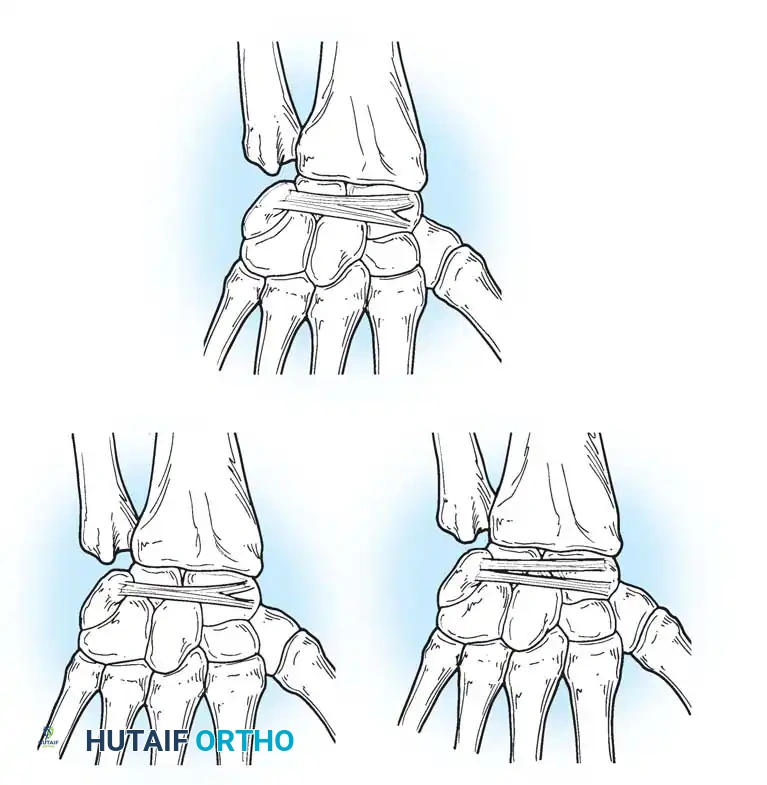

The Triangular Fibrocartilage Complex (TFCC)

The distal ulna articulates with the radius at the sigmoid notch, accommodating the ulnar head through approximately two-thirds of its rotational arc. The distal ulna is inclined at approximately 20 degrees relative to the radius.

Separating the hyaline cartilage-covered ulnar head from the carpus is the TFCC, a critical chondroligamentous stabilizer first comprehensively described by Palmer and Werner. The TFCC is the primary stabilizer of the DRUJ and the ulnar carpus.

Components of the TFCC

The TFCC is a multi-structural complex comprising:

* The Articular Disc (TFC proper): A biconcave fibrocartilaginous structure that absorbs axial loads (transmitting approximately 20% of the axial load across the wrist).

* Dorsal and Volar Radioulnar Ligaments: The primary stabilizers of the DRUJ during pronation and supination.

* Meniscus Homologue: A reflection of fibrous tissue extending from the dorsal radius to the volar carpus.

* Ulnar Collateral Ligament (UCL): Extending from the ulnar styloid to the pisiform and triquetrum.

* Extensor Carpi Ulnaris (ECU) Subsheath: Intimately blended with the dorsal aspect of the TFCC.

* Ulnolunate and Ulnotriquetral Ligaments: Volar extrinsic ligaments that prevent volar subluxation of the ulnar carpus.

Surgical Warning: When performing ulnar-sided surgical approaches or arthroscopy, extreme care must be taken to preserve the foveal attachments of the radioulnar ligaments. Disruption here leads to profound DRUJ instability that cannot be salvaged merely by repairing the articular disc.